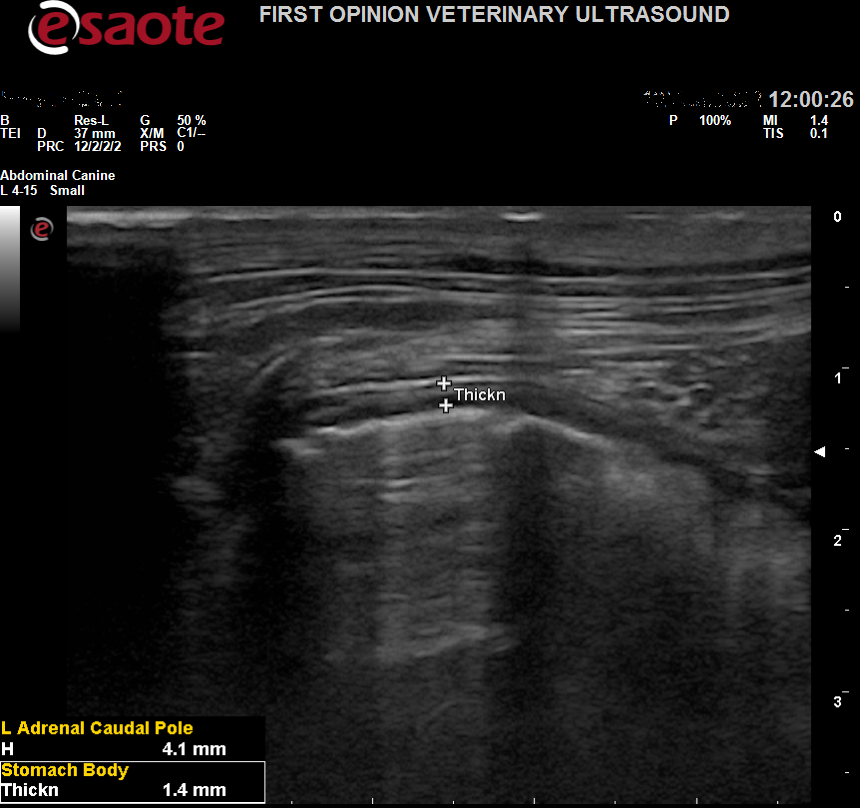

The Esaote MyLab Omega is a step up from the Sigma model. It is a portable version of the cart based machine X7. I was blown away by this machine. The Omega has immense image quality.

They have also introduced a preset that highlights gastrointestinal tract walls brilliantly and in great detail. The image quality is just outstanding, and it certainly is a step up from the Sigma and X5 models in image quality.

Images from the Omega